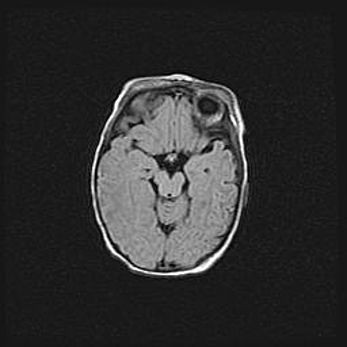

Церебральная ишемия II.

Возраст: 5 дней

Вес: 3400 г

Пол: женский

Окружность головы: 35 см

Срок гестации: 39 недель

Церебральная ишемия – это заболевание, характеризующееся недостаточностью (гипоксией) либо полным прекращением (аноксией) снабжения мозга кислородом по причине закупорки одного или нескольких сосудов. Это приводит к  что метаболическим расстройствам различной степени тяжести в тканях головного мозга, развитию коагуляционных некрозов и гибели нейронов.